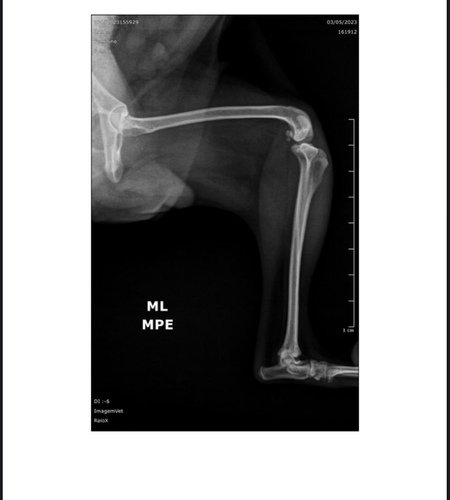

Eu sou a @zayaaugusto. Minha mãe @rosesoaresa criou essa vaquinha porque preciso arrecadar 2,500 reais para fazer duas cirurgias nos meus dois joelhos que deslocaram quando pulei da cama dela.. Agredeço a contribuição de todos! ver tudo

Eu sou a @zayaaugusto. Minha mãe @rosesoaresa criou essa vaquinha porque preciso arrecadar 2,500 reais para fazer duas cirurgias nos meus dois joelhos que deslocaram quando pulei da cama dela.. Agredeço a contribuição de todos!